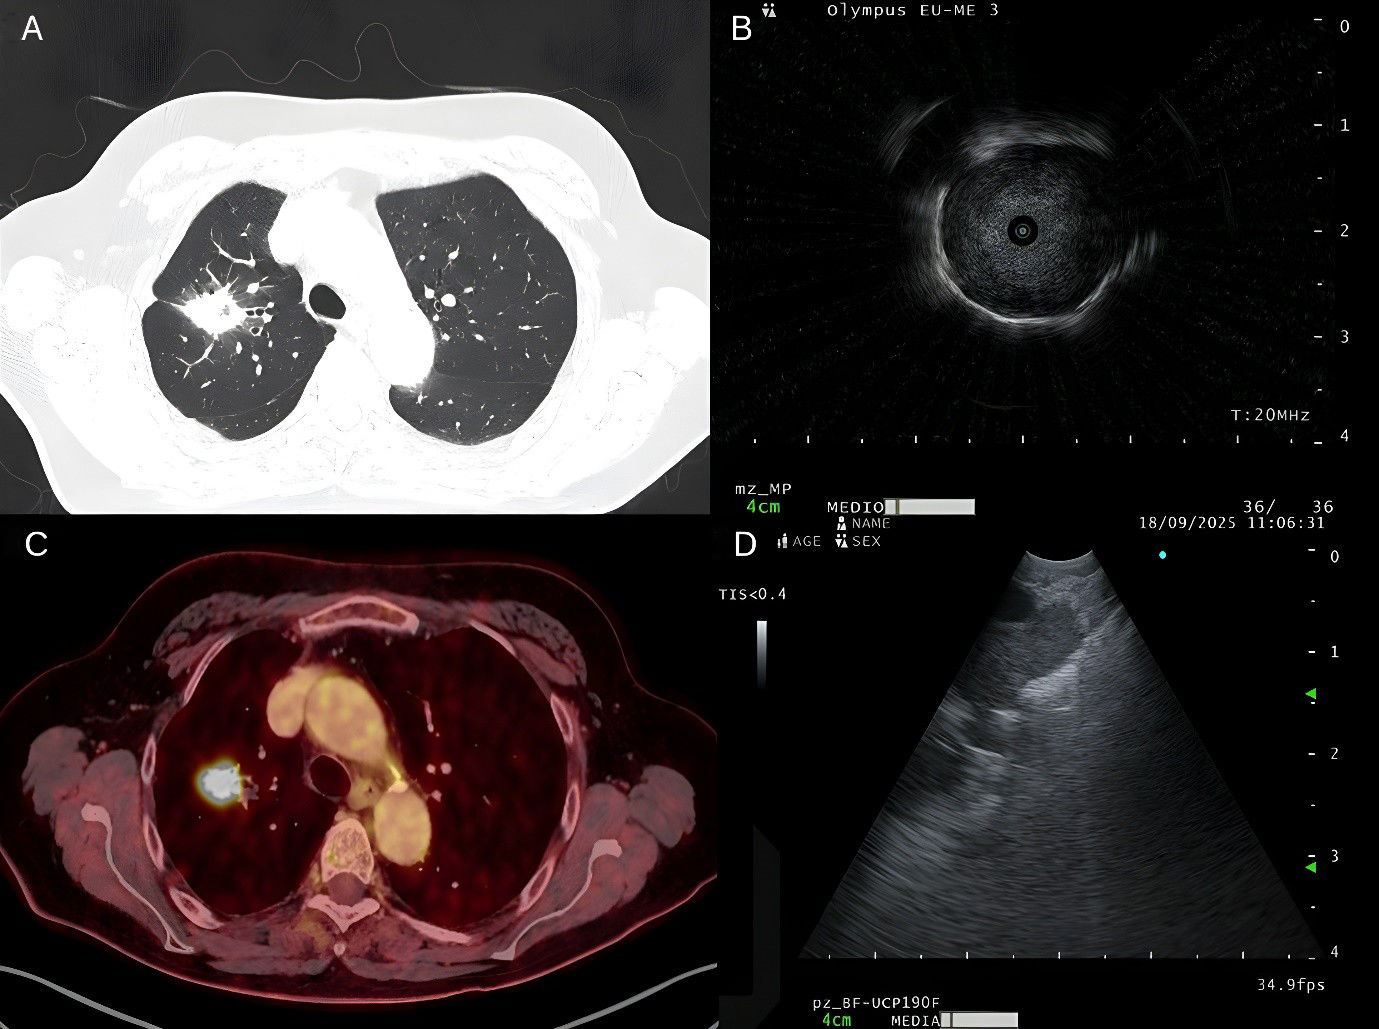

We report a 64-year-old Spanish male smoker (70 pack-years) with a history of HIV on antiretroviral therapy and hepatitis C-related cirrhosis grade 2. He was referred from Infectious Diseases following an asymptomatic high-risk screening chest CT in June 2025. Physical examination was unremarkable. Chest CT demonstrated a 31mm spiculated mass in the right upper lobe (RUL) with positive bronchus sign, focal scarring, and calcifications, without significant hilar or mediastinal lymphadenopathy (Fig. 1A). PET scan confirmed increased metabolic activity in the pulmonary mass (Fig. 1C). Initial flexible bronchoscopy with r-EBUS identified the lesion in the RUL apical sub-segment, but microbiological cultures showed no growth and brush cytology was negative for malignant cells. In a second bronchoscopy, we employed the Olympus BF-UCP190F, to navigate to the fifth bronchial generation within the RUL apical sub-segment (Fig. 1D). A hypoechoic lesion with hyperechoic borders was identified and sampled using a ViziShot2 25G needle (three passes). Subsequent r- EBUS (UM-S20-17S, Olympus) confirmed a hypoechoic lesion with air–lesion interface reflex distal to the puncture site (Fig. 1B). Cytology from peripheral EBUS-TBNA revealed abundant atypical epithelial cells consistent with non-small cell lung carcinoma. Finally, the patient was diagnosed with T2aN0M0 lung cancer and deemed suitable for surgical resection.

(A) Chest CT with a 31mm spiculated mass in the right upper lobe with positive bronchus sign. (B) Hypoechoic lesion with air-lesion interface in right upper lobe apical sub-segment. (C) PET-CT confirmed increased metabolic activity in 31mm speculated mass in the right upper lobe. (D) Hypoechoic lesion with hyperechoic borders in contact with the lumen of right upper lobe apical sub-segment.

The challenge of diagnosing PPLs has led to the development of advanced bronchoscopy-guided techniques, such as electromagnetic navigation bronchoscopy or robot-assisted bronchoscopy. Although these approaches can be effective, their cost and technical complexity limit their use in many hospitals. As illustrated in our case, which represents the first published report in Spain, the peripheral EBUS-TBNA bronchoscope may be a valuable alternative. This approach can complement the r-EBUS examination, and may even increase diagnostic yield in situations where the use of r-EBUS is limited by the absence of a bronchial sign [5]. In conclusion, this case demonstrates the potential of the new-generation EBUS bronchoscope to successfully navigate to and sample a pulmonary nodule in a very distal location. To our knowledge, this is the first published report demonstrating the feasibility of this technique for diagnosing a peripheral lung lesion. The ability to obtain a real-time ultrasound image and perform a guided needle aspiration of a parenchymal lesion so deep within the bronchial tree represents a significant technical advance.